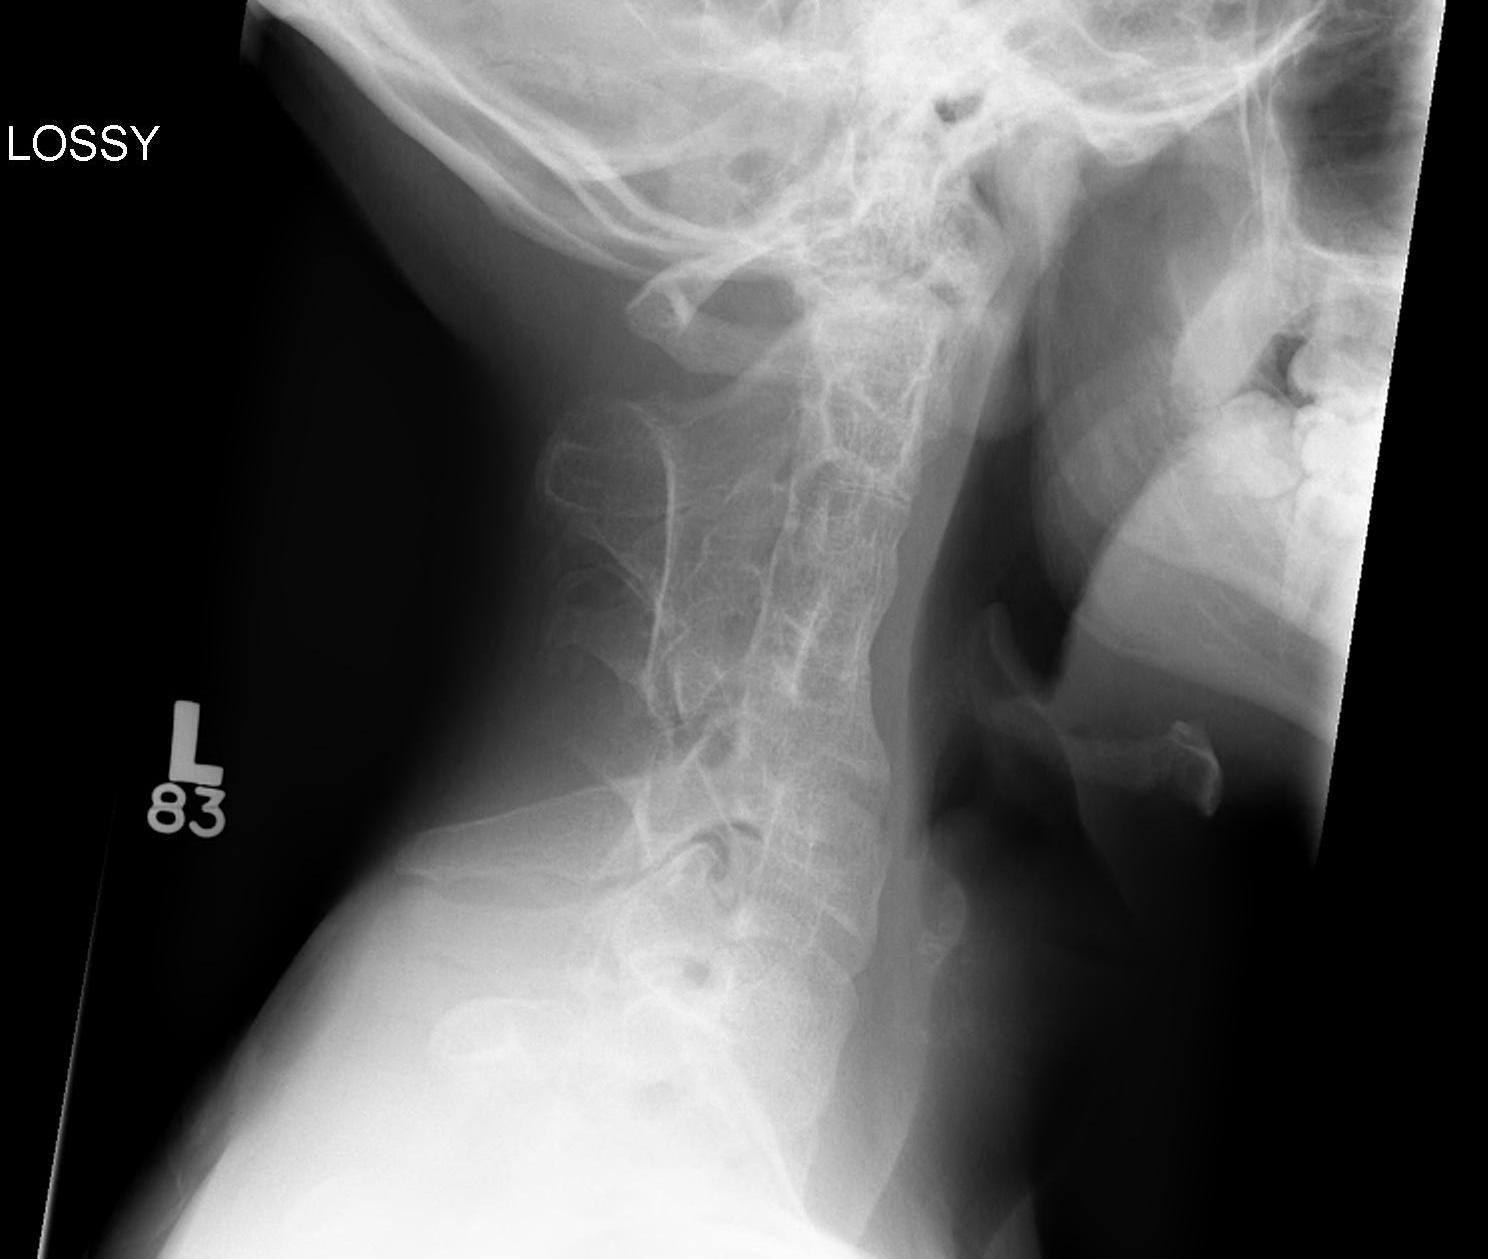

Xray

Vertebral fusions

Thoracic abnormalities

- scoliosis

- kyphosis